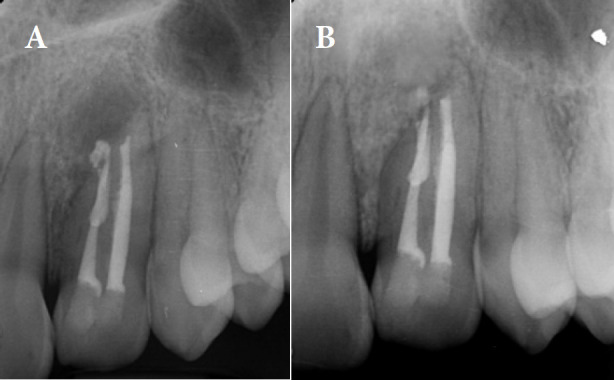

Dens invagination (DI) is a developmental dental anomaly characterized by the infolding of the enamel organ into the dental papilla. Type IIIb DI, involving deep invagination that extends apically along the root, poses significant challenges in endodontic treatment due to its complex anatomy. We describe a case of type IIIb DI in a 13-year-old female referred with the chief complaint of spontaneous pain on the left maxillary lateral incisor. Clinical examinations showed tenderness to percussion and palpation as well as a positive response to cold test with lingering pain. Cone-beam computed tomography (CBCT) confirmed the presence of type IIIb DI associated with a periapical lesion. The final diagnosis was irreversible pulpitis with apical periodontitis for main canal (distal) and pulpless and infected root canal system with secondary acute apical periodontitis according to Abbott classification for the other canal. Two separate access cavities were prepared with the guidance of CBCT. Root canal therapy was performed on both root canals, using photodynamic therapy (PDT) and ultrasonic-activated sodium hypochlorite for enhanced disinfection. Calcium-enriched mixture cement was used to obturate the apical third, followed by thermoplastic gutta-percha in the middle and coronal thirds. The patient was asymptomatic at 6- and 12-month follow-ups, with radiographic evidence of complete healing. This case highlights the effectiveness of conservative endodontic treatment using PTD in managing complex DI cases, with a focus on maintaining tooth structure and achieving long-term success.

Abstract Image